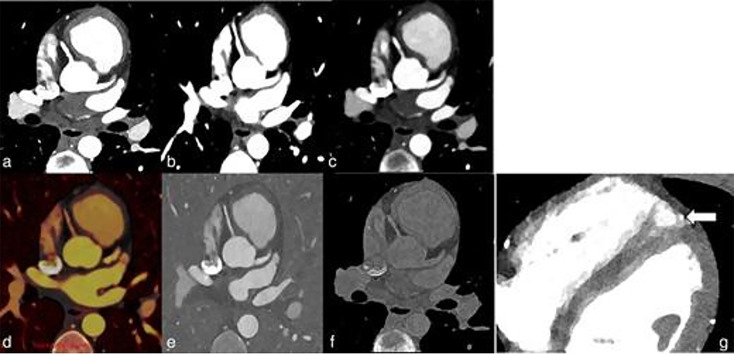

Photon-counting computed tomography (PCCT) represents a significant advancement in pediatric cardiovascular imaging. Traditional CT systems employ energy-integrating detectors that convert X-ray photons into visible light, whereas PCCT utilizes photon-counting detectors that directly transform X-ray photons into electric signals. This direct conversion allows photon-counting detectors to sort photons into discrete energy levels, thereby enhancing image quality through superior noise reduction, improved spatial and contrast resolution, and reduced artifacts. In pediatric applications, PCCT offers substantial benefits, including lower radiation doses, which may help reduce the risk of malignancy in pediatric patients, with perhaps greater potential to benefit those with repeated exposure from a young age. Enhanced spatial resolution facilitates better visualization of small structures, vital for diagnosing congenital heart defects. Additionally, PCCT's spectral capabilities improve tissue characterization and enable the creation of virtual monoenergetic images, which enhance soft-tissue contrast and potentially reduce contrast media doses. Initial clinical results indicate that PCCT provides superior image quality and diagnostic accuracy compared to conventional CT, particularly in challenging pediatric cardiovascular cases. As PCCT technology matures, further research and standardized protocols will be essential to fully integrate it into pediatric imaging practices, ensuring optimized diagnostic outcomes and patient safety.